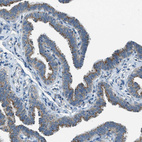

Immunohistochemical staining of human Fallopian tube shows strong granular cytoplasmic positivity in glandular cells.